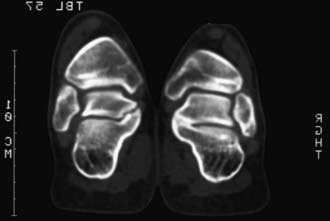

A fibrous coalition might require additional imaging studies to diagnose. Plain films may be diagnostic, but a CT scan is the imaging modality of choice when a coalition is suspected (Fig. 666-5). In addition to securing the diagnosis, this study helps to define the degree of joint involvement in patients with a talocalcaneal coalition. Coalitions are uncommon, but >1 tarsal coalition may be observed in the same patient.

image

Figure 666-5 CT scan of the talocalcaneal complex demonstrating tarsal coalition.